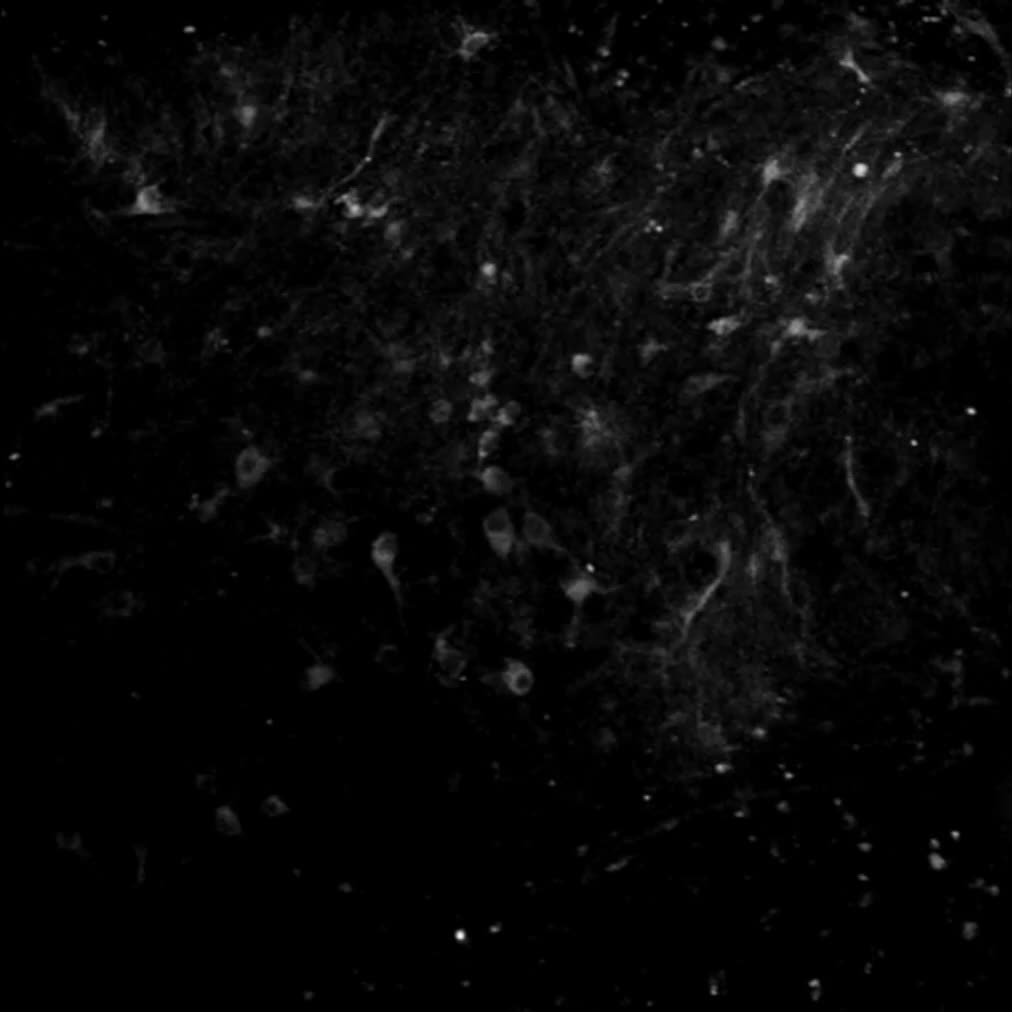

تصاویری از یک انقلاب شگفت‌انگیز در علم پزشکی